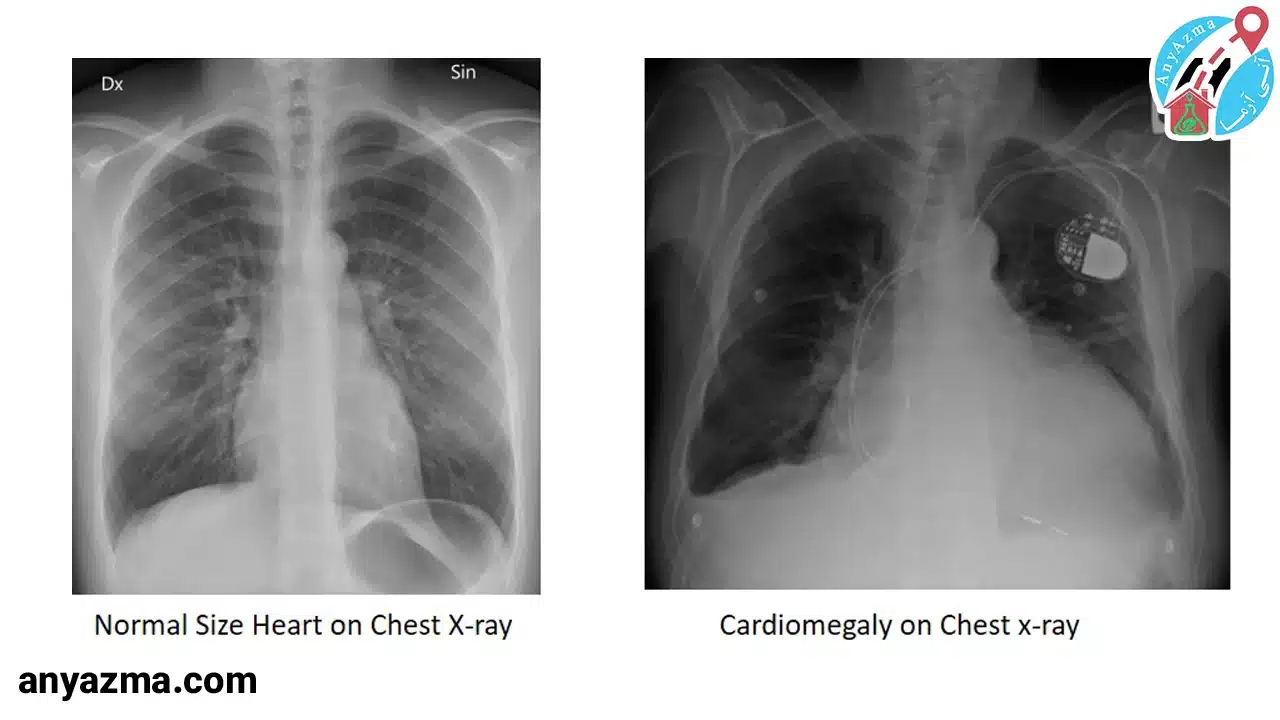

- عکس قفسه سینه (اشعه ایکس)

| 2 | عکس قفسه سینه (X-ray) | بررسی اندازه قلب و ریهها؛ تشخیص بزرگی قلب | سریع، ارزان، در دسترس | دقت متوسط؛ نمیتواند عملکرد قلب را نشان دهد |

بزرگ شدن قلب یا کاردیومگالی، به خودی خود یک بیماری نیست، بلکه نشانهای از وجود یک مشکل زمینهای دیگر است که قلب را تحت فشار قرار داده است.